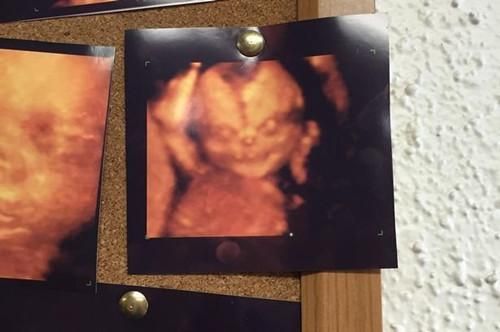

父母用4D超声波为胎儿拍照 现“恶魔宝宝”

艾伦原本想带着老婆尝试4D超音波技术,一睹未出世的宝宝可爱的照片,但却在等候室看到这张恶魔宝宝照,让他打消了念头。中新网8月17日电 据台湾“联合新闻网”报道,都说婴儿像天使,但看了国外一名即将成为爸爸的男子最近在社交网络上分享的胎儿4D超声波照,可能会让人们就此改观。宝宝空洞的眼神,阴险的微笑,头顶还有一个裂缝,就像个小恶魔,男子艾伦·詹姆士说:“我简直吓呆了。”

报道称,艾伦原本想带着老婆尝试4D超音波技术,一睹未出世的宝宝可爱的照片,但却在等候室看到这张恶魔宝宝照,让他打消了念头。有网友说:“一想到恶魔宝宝通过机器盯着父母瞧,就觉得毛骨悚然。”

据悉,曾有网友收集了许多会让父母心情一下从天堂掉到地狱的恐怖超声波照,但从妇产科医生的角度来看,宝宝的眼窝、鼻软骨,以及牙龈都还在发展,拍照的角度也会有影响,才会拍出恐怖的恶魔宝宝照片。

恶魔宝宝超声波照放到网上不到24小时,就吸引了超过52万人次的点击量,还有上百则留言讨论。网友直呼,以后和太太只要用传统的超声波就好,以免拍出让人后悔的恐怖宝宝。(中国新闻网)